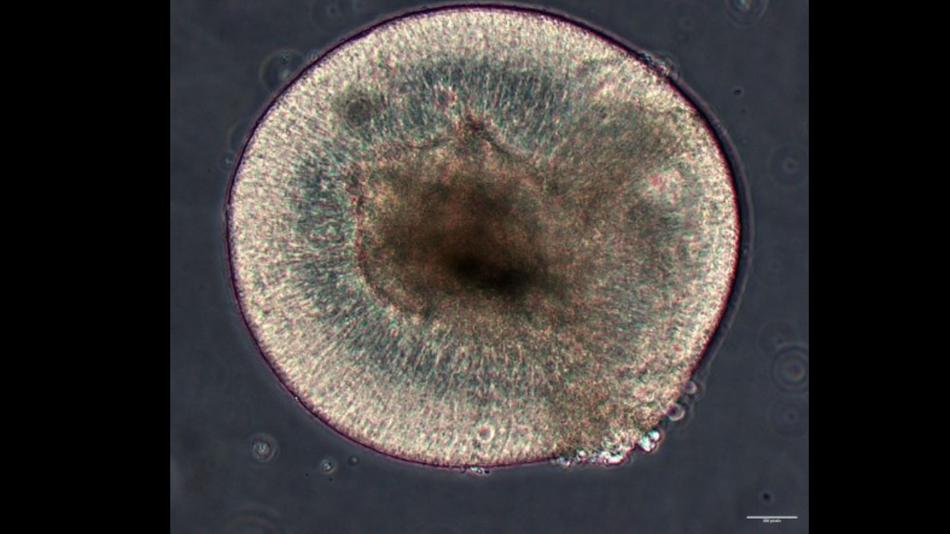

Wie kann man ohne Tierversuche Blindheit erforschen?

An dieser Station zeigen wir, wie diese Methode in unserem Labor praktisch umgesetzt wird.